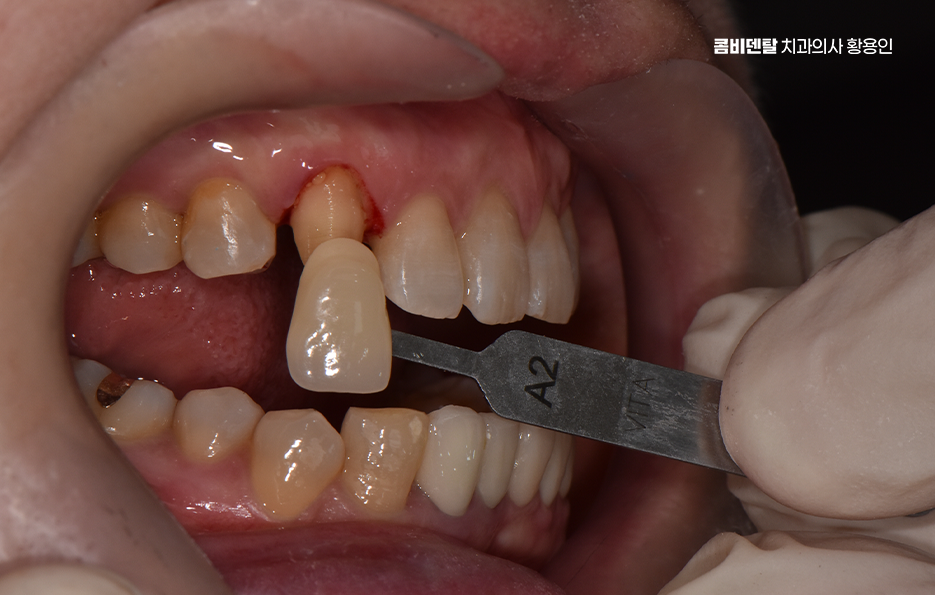

특히 송곳니 크라운 치료가 필요한 상황이라면, 단순히 기능 회복만 생각할 게 아니라 모양과 색감까지 자연스럽게 복원하는 게 중요하겠고 이런 경우에 적합한 방법이 바로 올세라믹이나 지르코니아 크라운을 이용한 심미적인 치료라고 할 수 있어요

크라운 치료는 치아가 많이 손상됐을 때, 또는 신경치료 후 치아가 약해졌을 때 치아를 보호하고 형태를 회복시키기 위한 보철 치료인데 쉽게 말하면 보통 씌우기 치료라고 말하는 치아를 보철물로 전체를 덮는 치료로 송곳니처럼 앞쪽에 위치한 치아는 씌운 게 티 나지 않게 만들어야 하니까 재료 선택이 중요하다는 점에서도 올세라믹과 지르코니아 같은 재료가 주로 활용되고 있었어요

올세라믹 크라운은 말 그대로 금속이 전혀 들어가지 않은 세라믹 재료로 만들어진 크라운으로 금속 없이 순수한 도자기로만 제작되기 때문에 빛 투과성이 자연치아와 거의 비슷하고, 치아 본연의 반투명한 느낌을 재현할 수 있으며 특히 송곳니처럼 햇빛이나 형광등 아래에서 드러나기 쉬운 치아는 빛에 반응하는 느낌이 중요한데 올세라믹은 이런 부분에서 우수한 심미성을 보여주는 재료로 말할 때나 웃을 때 자연스럽게 어우러져서 보철물이 있다는 걸 거의 눈치챌 수 없게 만들어줄 수 있을 정도로 송곳니 크라운 재료에서 심미적인 장점이 있어요

그리고 물론 치료 과정도 중요한데 아무리 좋은 재료를 써도, 본을 잘못 뜨거나 치아 삭제량이 과하면 치아의 수명도 더 줄어들 수 밖에 없고 결과가 자연스럽지 않을 수 있으며 송곳니는 치근이 길고, 뿌리 방향이 독특한 구조를 가지고 있기 때문에 섬세하고 정교한 치료가 중요하기 때문에 경험 많은 치과의사와 함께 하는 것도 중요한 부분이라 할 수 있었어요

송곳니 크라운 치료 시에 자연스러운 결과를 위해 고려해야 할 점으로 또 하나는 잇몸과의 조화로 예를 들어 금속이 들어간 PFM과 같은 보철물은 시간이 지나면서 잇몸 경계에 어둡게 변색되는 현상이 생길 수 있지만 올세라믹은 전혀 금속이 없기 때문에 이런 문제가 없고, 인체 친화적인 소재라 잇몸 자극도 거의 없으며 송곳니는 입술과 접촉이 많은 위치라서 잇몸이 예민한 편인데 올세라믹은 이런 잇몸과도 안정적인 조화를 이루기 때문에 오랜 시간이 지나도 건강한 상태를 유지할 수 있다는 점에서 장점이 있어요